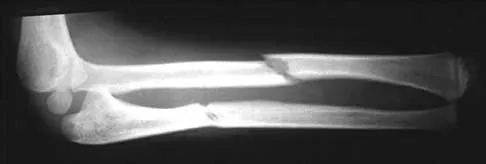

A 17-year-old high school football player reports wrist pain after being tackled. Radiographs are shown in Figures 22a through 22c. What is the recommended intervention?

Explanation

The patient has an acute fracture of the proximal pole. A 100% healing rate has been reported for open reduction and internal fixation of proximal pole fractures via a dorsal approach. This allows for direct viewing of the fracture line, facilitates reduction, and bone grafting can be done through the same incision if necessary. A vascularized or corticocancellous graft is reserved for nonunions. Proximal fractures are very slow to heal with a cast, if they heal at all. As a small fragment, percutaneous fixation is very difficult and has been reported for waist fractures. Rettig ME, Raskin KB: Retrograde compression screw fixation of acute proximal pole scaphoid fractures. J Hand Surg Am 1999;24:1206-1210.